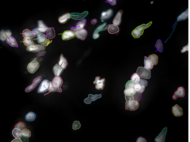

Imaging Platform

The central imaging core facility at the MPI for heart and lung research, provides a wide range of services and trainings, project specific support and full services for more than 100 scientists at the institute as well as for their collaboration partners. We also offer training for image analysis, develop custom analysis pipelines and help with data storage and archiving.